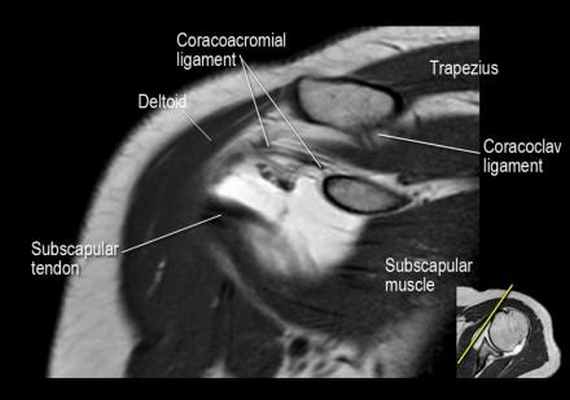

Изображение передних отделов плечевого сустава.

Сухожилие подлопаточной мышцы прикрепляется как к малому бугорку, так и к большому бугорку, давая поддержку длинной головке двуглавой мышцы в борозде двуглавой мышцы. Вывих длинной головки двуглавой мышцы плеча неизбежно приведет к разрыву части подлопаточной сухожилия. Манжета вращателей плеча состоит из сухожилий подлопаточной, надостной, подостная и малой круглой мышц.

Нормальная корональная анатомия плечевого сустава и контрольный список

- обратите внимание на клюво-ключичную связку (coracoclavicular ligament) и короткую головку двуглавой мышцы (short head of the biceps).

- обратите внимание на клювоакромиальную связку (coracoacromial ligament).